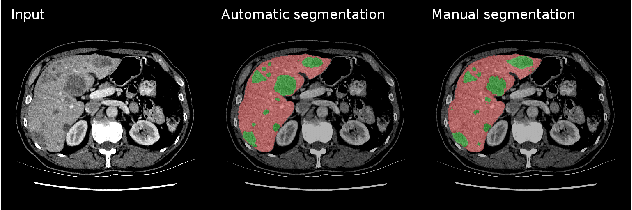

Abstract:In this work, we report the set-up and results of the Liver Tumor Segmentation Benchmark (LITS) organized in conjunction with the IEEE International Symposium on Biomedical Imaging (ISBI) 2016 and International Conference On Medical Image Computing Computer Assisted Intervention (MICCAI) 2017. Twenty four valid state-of-the-art liver and liver tumor segmentation algorithms were applied to a set of 131 computed tomography (CT) volumes with different types of tumor contrast levels (hyper-/hypo-intense), abnormalities in tissues (metastasectomie) size and varying amount of lesions. The submitted algorithms have been tested on 70 undisclosed volumes. The dataset is created in collaboration with seven hospitals and research institutions and manually reviewed by independent three radiologists. We found that not a single algorithm performed best for liver and tumors. The best liver segmentation algorithm achieved a Dice score of 0.96(MICCAI) whereas for tumor segmentation the best algorithm evaluated at 0.67(ISBI) and 0.70(MICCAI). The LITS image data and manual annotations continue to be publicly available through an online evaluation system as an ongoing benchmarking resource.

Abstract:We propose a model for the joint segmentation of the liver and liver lesions in computed tomography (CT) volumes. We build the model from two fully convolutional networks, connected in tandem and trained together end-to-end. We evaluate our approach on the 2017 MICCAI Liver Tumour Segmentation Challenge, attaining competitive liver and liver lesion detection and segmentation scores across a wide range of metrics. Unlike other top performing methods, our model output post-processing is trivial, we do not use data external to the challenge, and we propose a simple single-stage model that is trained end-to-end. However, our method nearly matches the top lesion segmentation performance and achieves the second highest precision for lesion detection while maintaining high recall.

Abstract:In this paper, we introduce a simple, yet powerful pipeline for medical image segmentation that combines Fully Convolutional Networks (FCNs) with Fully Convolutional Residual Networks (FC-ResNets). We propose and examine a design that takes particular advantage of recent advances in the understanding of both Convolutional Neural Networks as well as ResNets. Our approach focuses upon the importance of a trainable pre-processing when using FC-ResNets and we show that a low-capacity FCN model can serve as a pre-processor to normalize medical input data. In our image segmentation pipeline, we use FCNs to obtain normalized images, which are then iteratively refined by means of a FC-ResNet to generate a segmentation prediction. As in other fully convolutional approaches, our pipeline can be used off-the-shelf on different image modalities. We show that using this pipeline, we exhibit state-of-the-art performance on the challenging Electron Microscopy benchmark, when compared to other 2D methods. We improve segmentation results on CT images of liver lesions, when contrasting with standard FCN methods. Moreover, when applying our 2D pipeline on a challenging 3D MRI prostate segmentation challenge we reach results that are competitive even when compared to 3D methods. The obtained results illustrate the strong potential and versatility of the pipeline by achieving highly accurate results on multi-modality images from different anatomical regions and organs.